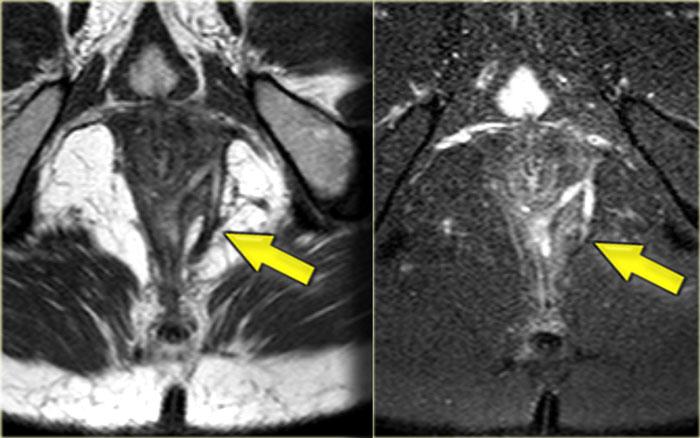

Bên trái là hình ảnh cắt ngang chuỗi xung T2W và T2W kết hợp xóa mỡ của một đường rò xuyên cơ thắt.

Khuyết hổng qua cơ thắt trong và cơ thắt ngoài ở vị trí 6 giờ hiện rõ và nổi bật hơn trên hình ảnh xóa mỡ.

Bên trái là hình ảnh cắt ngang chuỗi xung T2W xóa mỡ của một đường rò xuyên cơ thắt với lỗ mở niêm mạc ở vị trí 11 giờ.